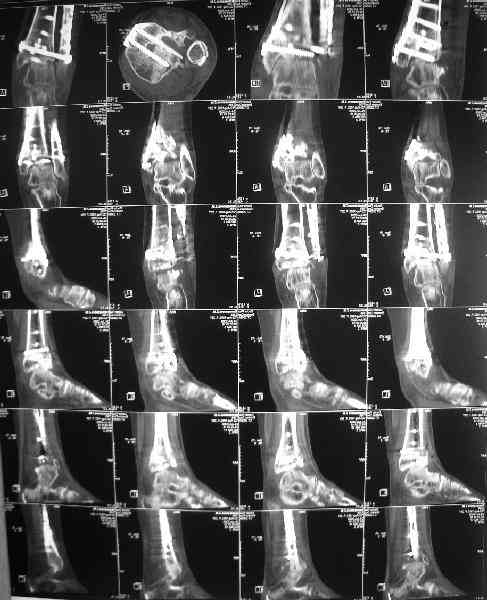

Обратилась женщина, 25 л. 8 мес. назад в одной из больниц сделан

остеосинтез пилона. На сегодня ходит без дополнительной опоры, хромая

на поврежденную ногу. Движения в голеностопном суставе еще есть.

Снимки в приложении.

Вопрос - что делать? Замыкать сустав пациентка пока не настроена

(наверно, получится настроить, если задаться такой целью). Нет ли

смысла попытаться сделать какую-то восстановительную операцию?

Допустим, получится устранить подвывих, восстановить межберцовые

соотношения - это что-то хорошее надолго даст? Или упросто убрать

"железо", и этим ограничиться, пока сама не придет за артродезом?

Есть ли здесь смысл пытаться организовать эндопротезирование? В

смысле, доступные сейчас протезы применимы в этой ситуации?